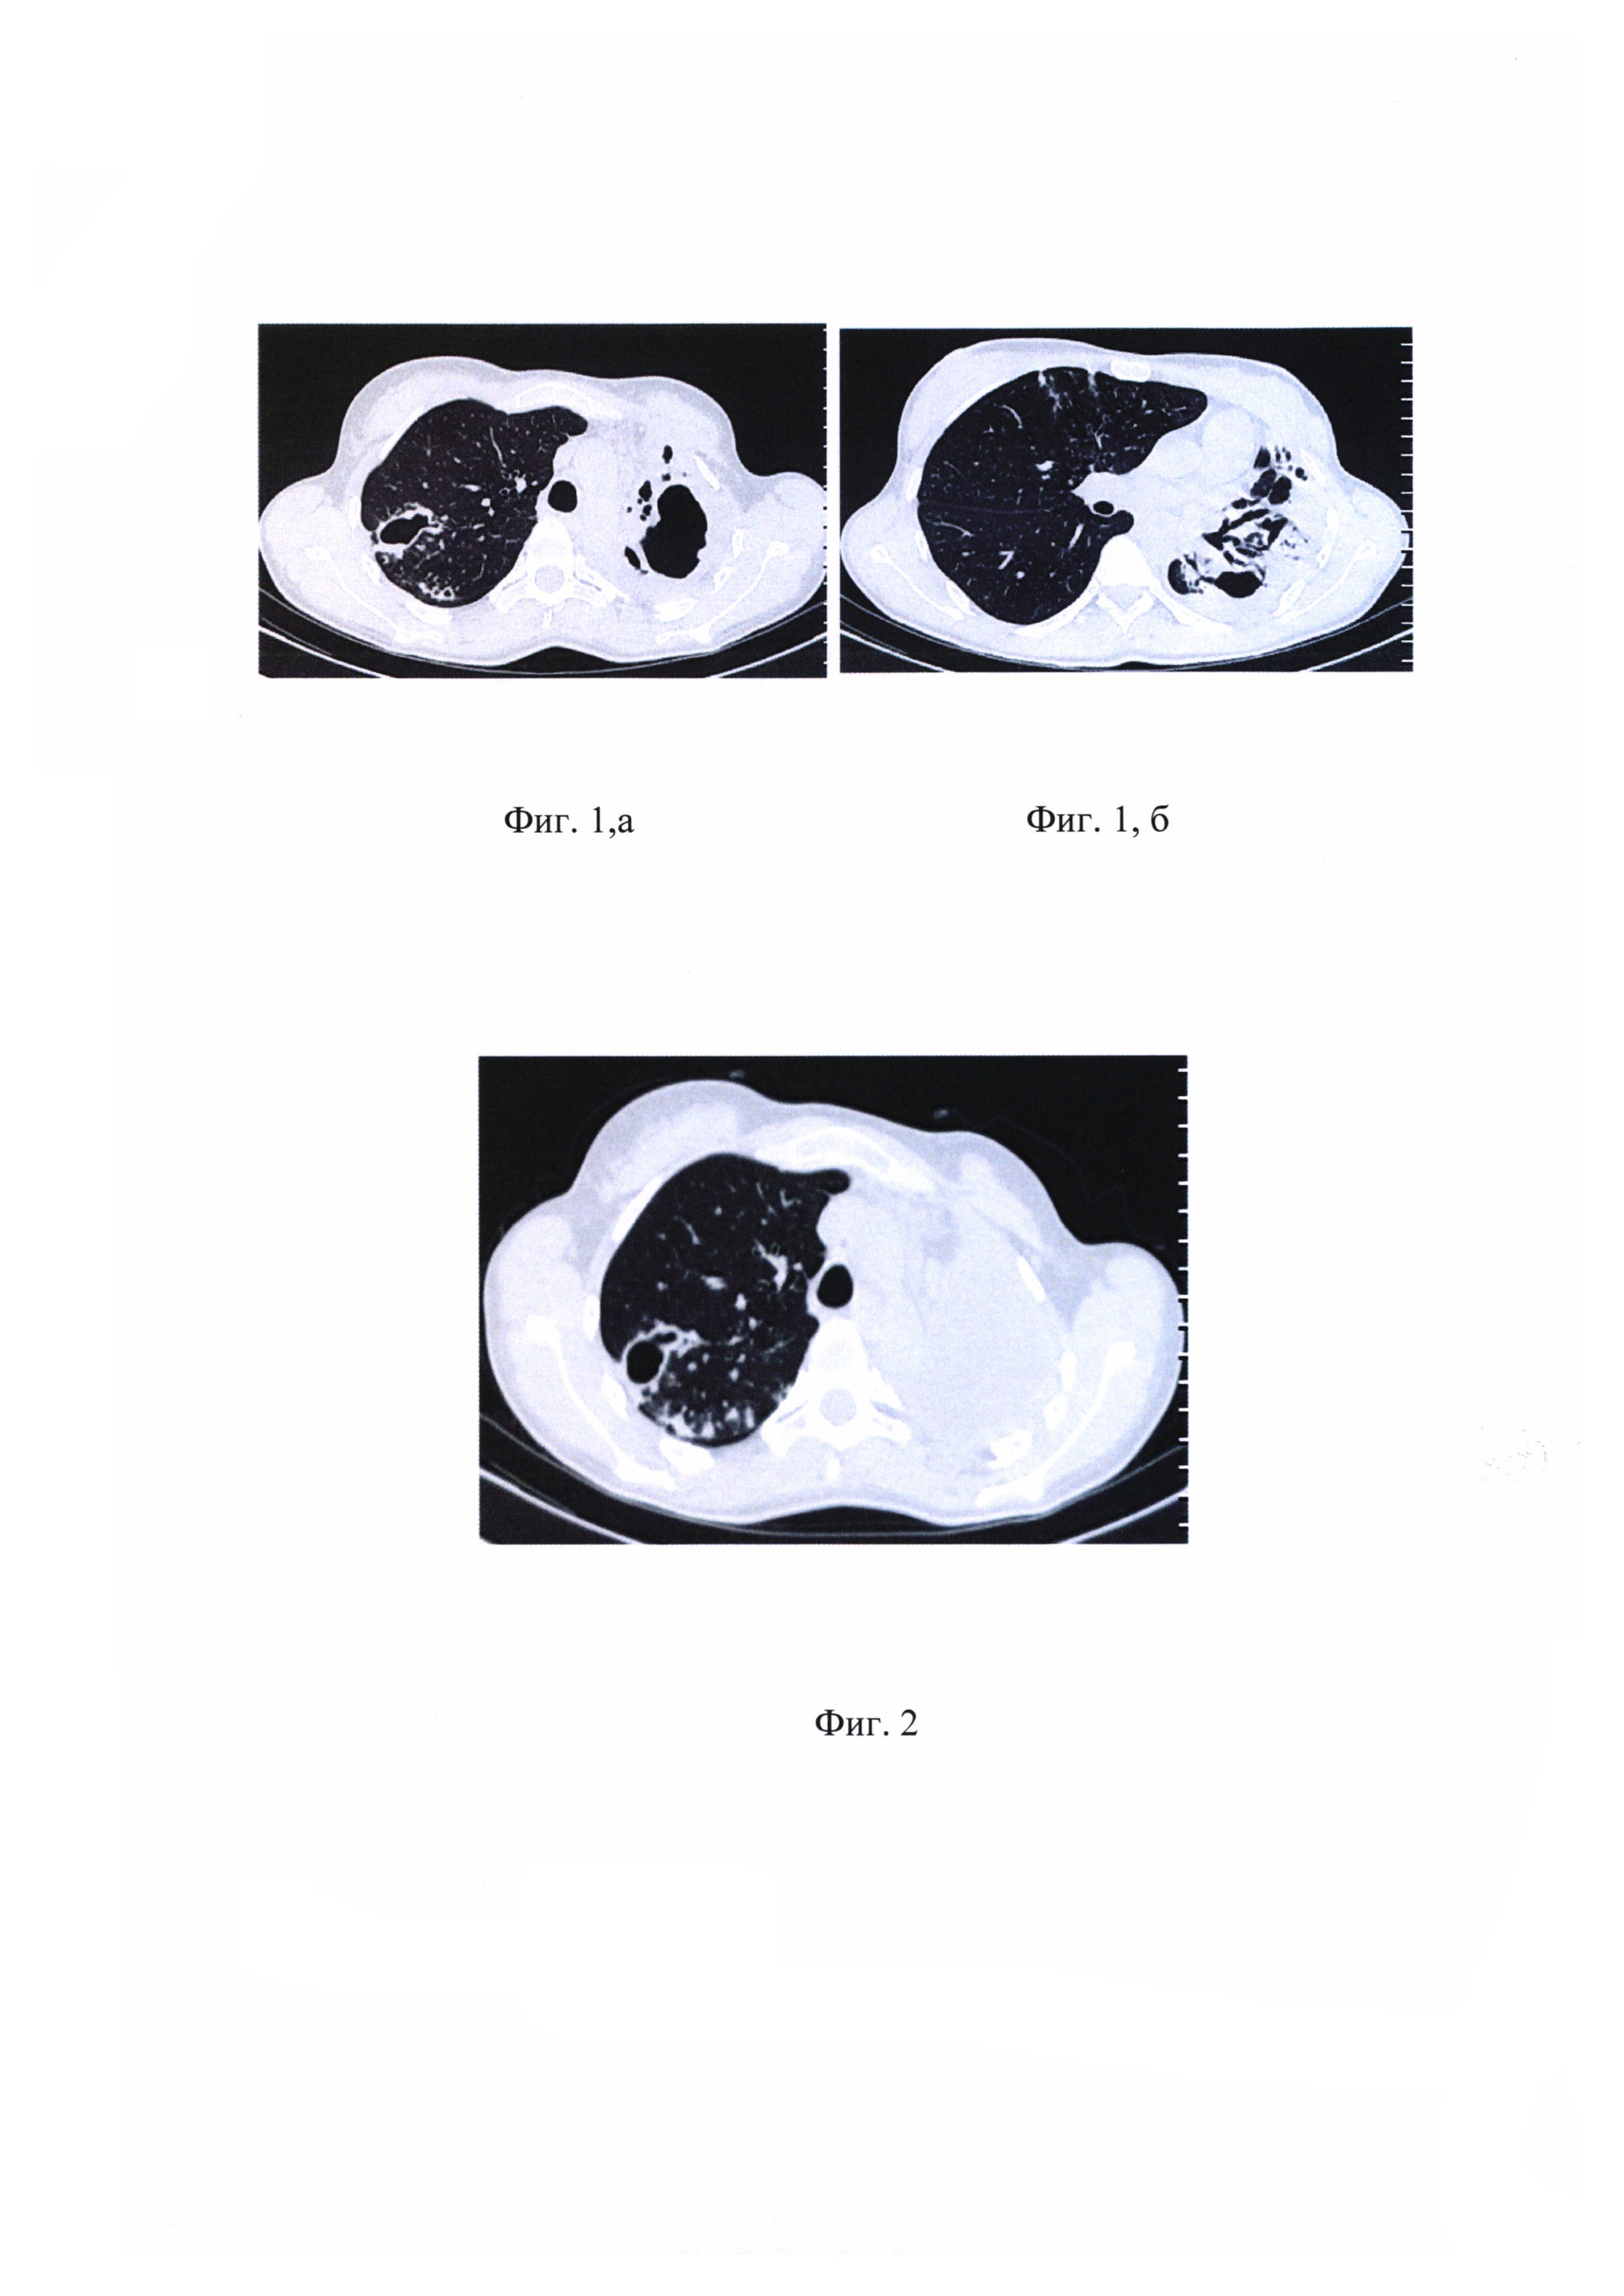

на фиг 3, а - обзорная рентгенограмма органов грудной клетки, каверна в правом легком находится в состоянии и компрессии, полостных, а также инфильтративных и очаговых изменений в единственном легком не определяется;

на фиг. 3, б - КТ органов грудной клетки, каверна в правом легком находится в состоянии и компрессии, полостных, а также инфильтративных и очаговых изменений в единственном легком не определяется.

На фиг 3, а - обзорная рентгенограмма органов грудной клетки, каверна в правом легком находится в состоянии и компрессии, полостных, а также инфильтративных и очаговых изменений в единственном легком не определяется. На фиг. 3, б - КТ органов грудной клетки, каверна в правом легком находится в состоянии и компрессии, полостных, а также инфильтративных и очаговых изменений в единственном легком не определяется.